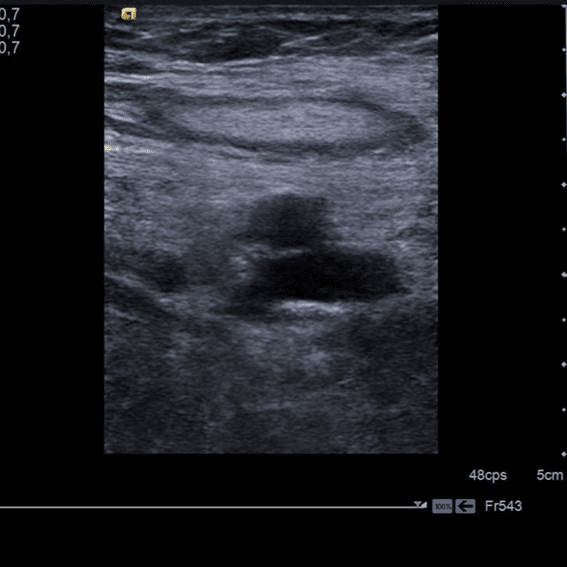

⚠️ Por tanto, tenemos una imagen con arteria (pulsátil en doppler) en plano profundo y un vaso sin flujo más superficial. Por esta distribución de vena superficial a la arteria, podemos confirmar que es la vena poplítea trombosada, no comprimible y sin doppler.